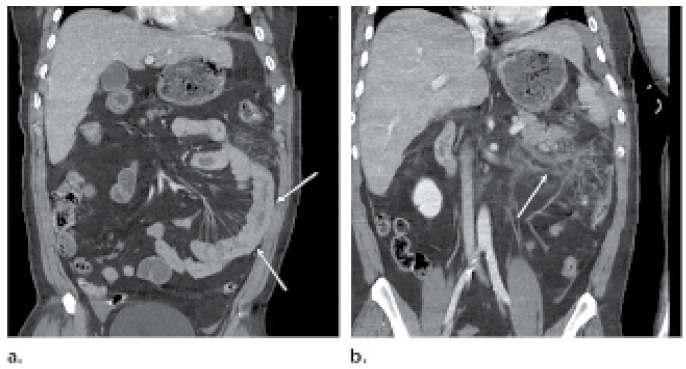

Multidetector CT of Surgically Proven Blunt Bowel and Mesenteric Injury

Blunt bowel and mesenteric injury is relatively uncommon in the setting of blunt abdominal trauma. However, a timely diagnosis is paramount to the proper triage and management of trauma patients.

In the March-April issue of RadioGraphics (RSNA.org/RadioGraphics), David D. B. Bates, MD, of Boston University Medical Center, and colleagues identify and describe three mechanisms of blunt bowel and mesenteric injury; discuss the sensitivity and specificity of various CT findings of blunt bowel and mesenteric injury; and discuss ways to recognize potential pitfalls in the evaluation of patients who are suspected of having blunt bowel and mesenteric injury.

Despite the relatively low rate of blunt bowel and mesenteric injury in patients with abdominal and pelvic trauma, delays in diagnosis are associated with increased rates of sepsis, a prolonged course in the intensive care unit and increased mortality.

“Once radiologists are familiar with the spectrum of findings of blunt bowel and mesenteric injury, they will be able to make timely diagnoses that will lead to improved patient outcomes,” the authors write.